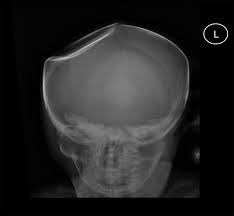

flat bone

broad & thin; cranial (frontal bone)

depressed fracture

dent in skull